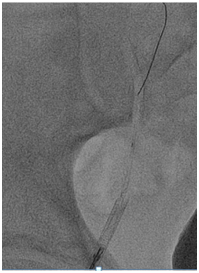

A 66-year old male with long standing history of type 2 diabetes, hypertension, dyslipidaemia and ischemic heart disease with prior history acute myocardial infarction treated with primary PCI to LAD with 3.0x22 mm drug eluting stent. Came for a staged PCI for a significant proximal RCA lesion. Following obtaining an informed consent and reload with 300 mg of Plavix. Right radial approach was selected patient received 7000 units of heparin. A 3DRCguidingcatheter was used to intubate the RCA following failure to engage with Judkin 4 guiding catheter, BMW wire advanced all the way to the distal end of RCA, lesion predilated by2.5x15mm compliant balloon to 12 atmospheres (Figure 1). A 3.5x 22mm Xience expedition stent was placed across the lesion under fluoroscopy. It was noted that the guide was not stable. It was decided to deploy the stent with the first fluoroscopy the stent appeared to have dislodged into the ascending aorta with the wire (Figure 2). Now the stent with an inflated balloon the guiding catheter and the wire all hanging in the ascending aorta. The initial decision to remedy this was to carefully and slowly withdraw the entire system along the course of the subclavian system and deploy the stent in a safe spot (Figure 3). But because of tortuosity it was thought to snare the entire system through a large femoral sheath. An 8 Fsheath was inserted into the right femoral artery and a 6 F ensnare system taken to the ascending aorta and grabbed the inflated balloon (Figure 4) and stent slowly moved down into the abdominal aorta under fluoroscopy. Then the balloon was deflated slowly and the snare tightened across the stent (Figure 5) and taken outside the body through the 8 F sheath (Figure 6) post snare femoral angiogram showed no injury to the femoral artery and a successful snaring of the dislodged stent. Patient was brought at alater date for a successful direct PCI to the RCA. This time the guide selected was an Amplatzer 0.75 (Figure 7).

Figure 3 Attempt to withdraw the stent and deploy in the right subclavian artery.